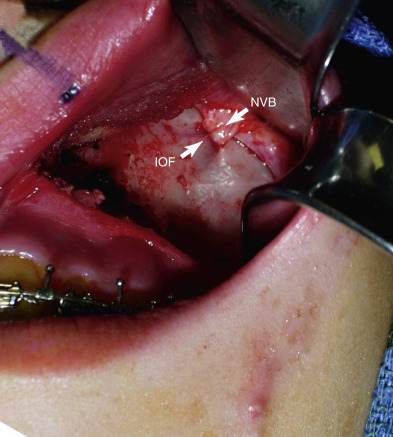

When beginning the subperiosteal dissection, it is not necessary to dissect medially to the pyriform (also spelled piriform) aperture (nasal region), because no part of the implant lies in this region in the average patient. The subperiosteal dissection is begun in the anterior maxillary region, and the initial dissection vector is superior, hence it is important to protect the infraorbital neurovascular bundle ( Fig. 7.11 ). The infraorbital nerve lies approximately 5–8 mm inferior to the infraorbital rim in line with the medial limbus ( Fig. 7.12 ). The implants are configured to lie inferior to the infraorbital nerve, and therefore aggressive infraorbital dissection is unnecessary.